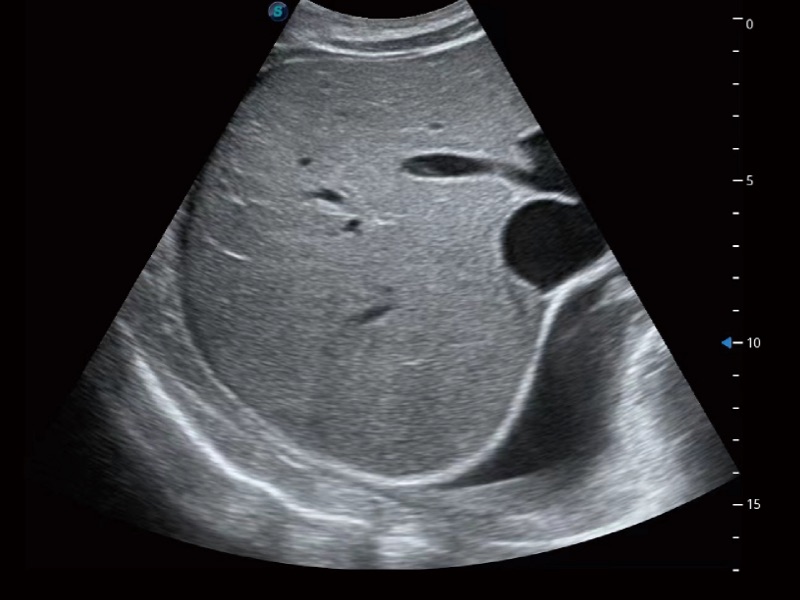

腹部应用

微米成像技术大大提高了器官和病变的可见性。高清对比度分辨率将抑制斑点噪声,同时保持真实的组织结构。